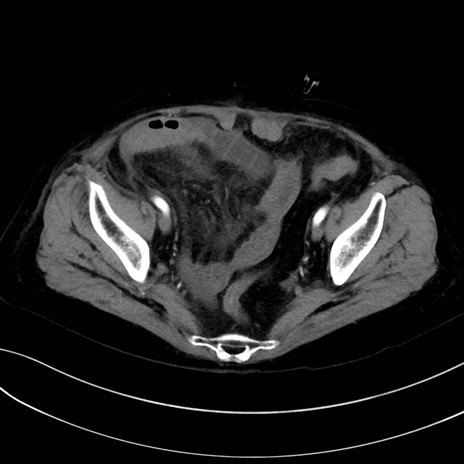

(冠状断像)1日半後